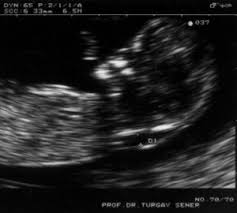

ultrasonda bebeğin burun kemiği

ultrasonda bebeğin burun kemiği.

prof dr k turgay sener kadin hastaliklari ve dogum perinatoloji uzmani tarama testleri degerlendirilmesi